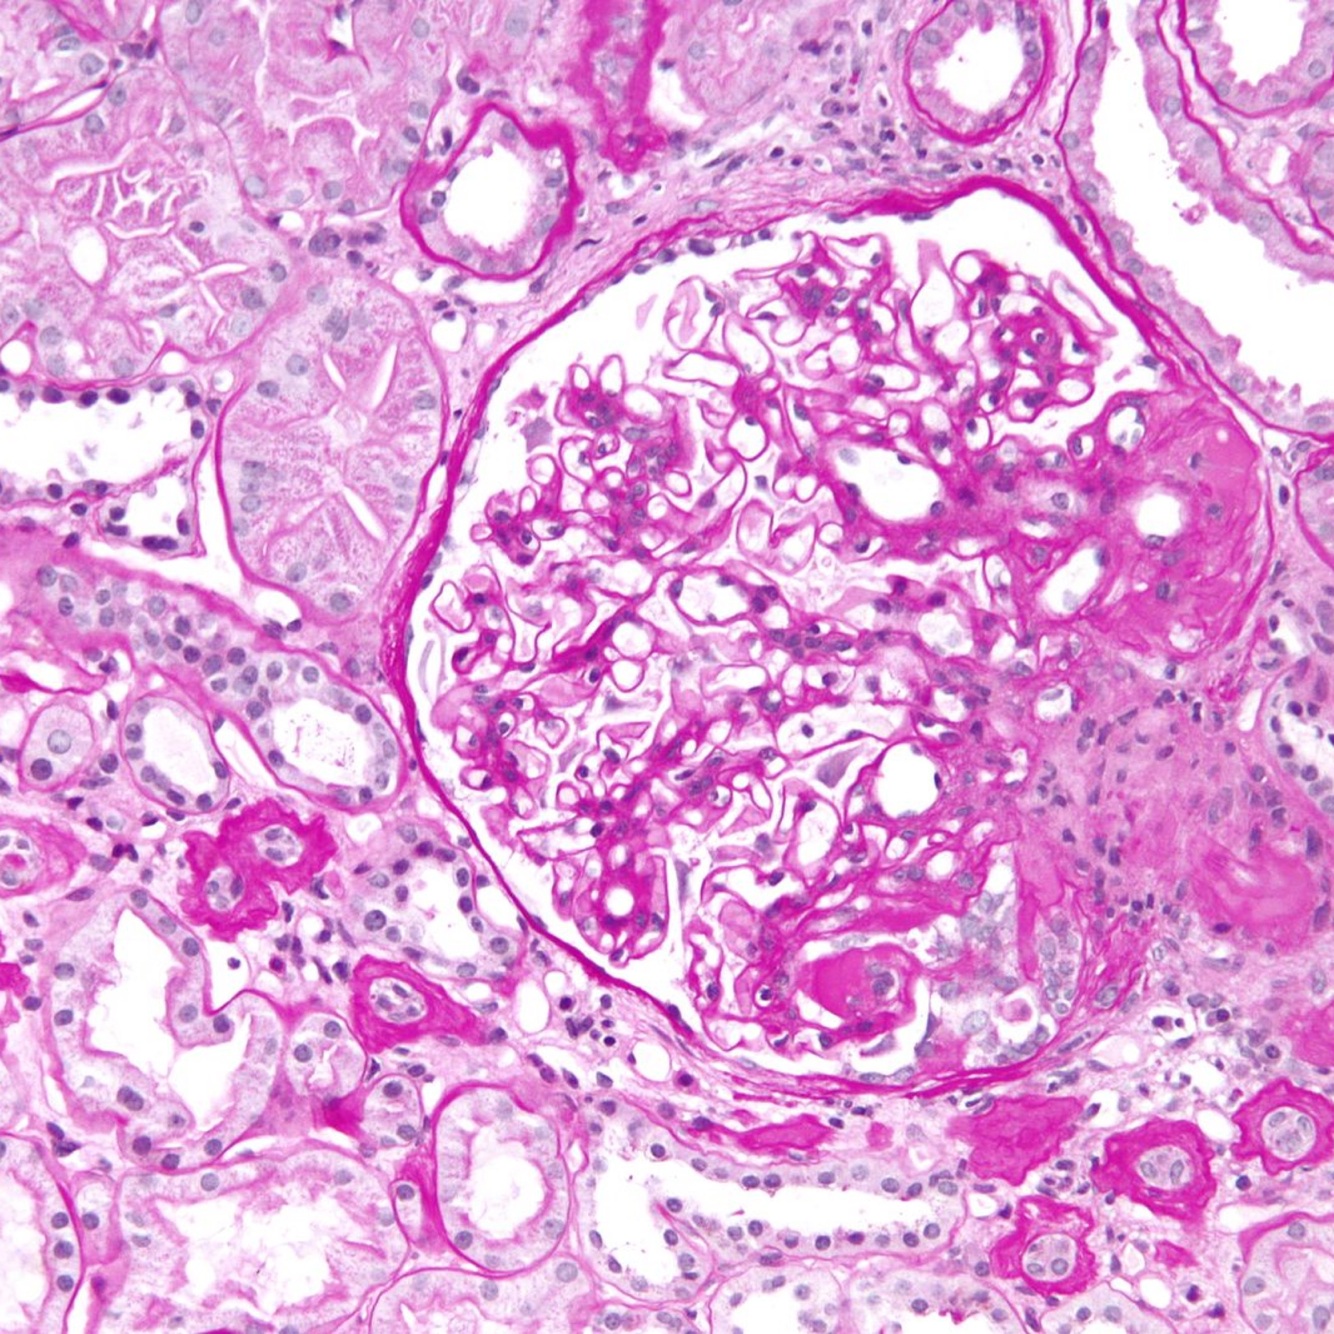

renal biopsy shows nodular sclerosis (also called Kimmelstiel-Wilson nodules), which is characteristic of advanced diabetic nephropathy